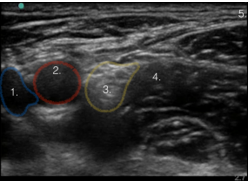

1. Vena femoral

2. Arteria femoral

3. Nervio femoral

4. Músculo ilíaco